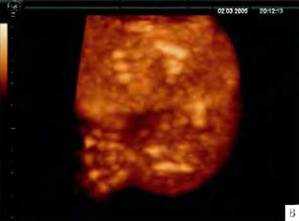

Рис. 20.2. Танатофорная дисплазия. А - трехмерная реконструкция. Б - поверхностная реконструкция укороченной левой руки плода. В - режим максимальной интенсивности. Видно укорочение трубчатых костей руки плода. Г - режим поверхностной реконструкции лица плода. Видна макроцефалия с выступающим лбом и западением корня носа.

Рис. 20.3. Танатофорная дисплазия. А и Б - поверхностная реконструкция. Видны укороченные конечности и узкая грудная клетка. В - фенотип абортуса.